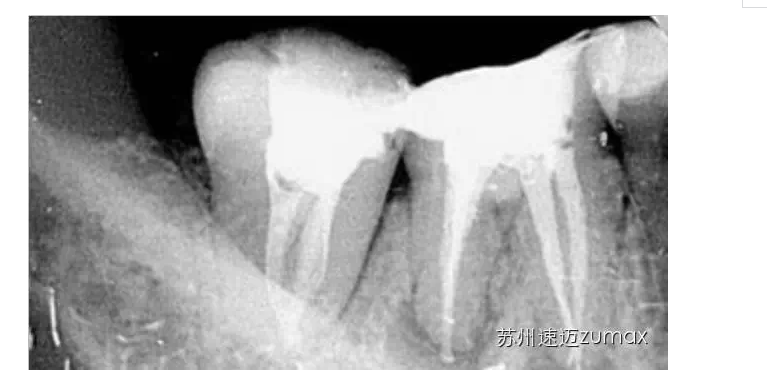

二、C形根管的識(shí)別

成功治療C形根管的前提是要正確識(shí)別,即判斷C形根管是否存在以及大致形態(tài)。僅從臨床牙冠的形態(tài)很難判斷C形根管是否存在,可通過(guò)X線技術(shù)、顯微鏡或內(nèi)窺鏡檢查以及CBCT檢查識(shí)別C形根管。

C形根管的治療最好是在手術(shù)顯微鏡下進(jìn)行。上橡皮障后開(kāi)髓,去除髓室中的牙髓組織,使用DG16仔細(xì)探查根管口位置,然后用10或15號(hào)不銹鋼K銼探查根管的形態(tài)、直徑和走向。當(dāng)根管口呈連續(xù)的C形時(shí),插入根管內(nèi)的診斷銼為2~4個(gè),通常為3個(gè)。當(dāng)根管口呈分號(hào)形時(shí),可以在較小的根管內(nèi)插入1個(gè)診斷銼,在較大的根管內(nèi)插入1~3個(gè)診斷銼。